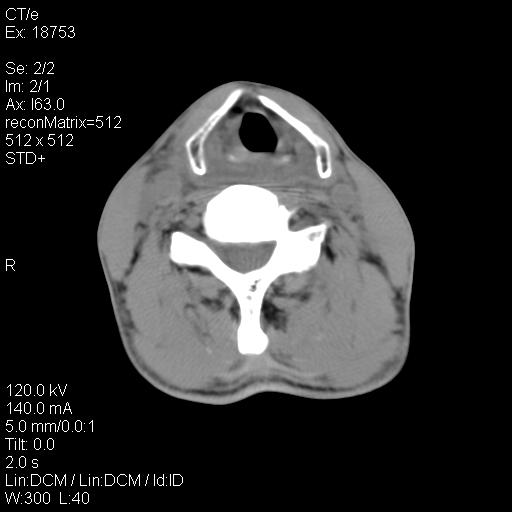

标题: CT21693:男 58岁 右侧咽部疼她2天余 PE:右侧扁桃体肿大 压痛 [打印本页]

标题: CT21693:男 58岁 右侧咽部疼她2天余 PE:右侧扁桃体肿大 压痛

右化脓性扁桃体炎症伴咽后壁脓肿形成.